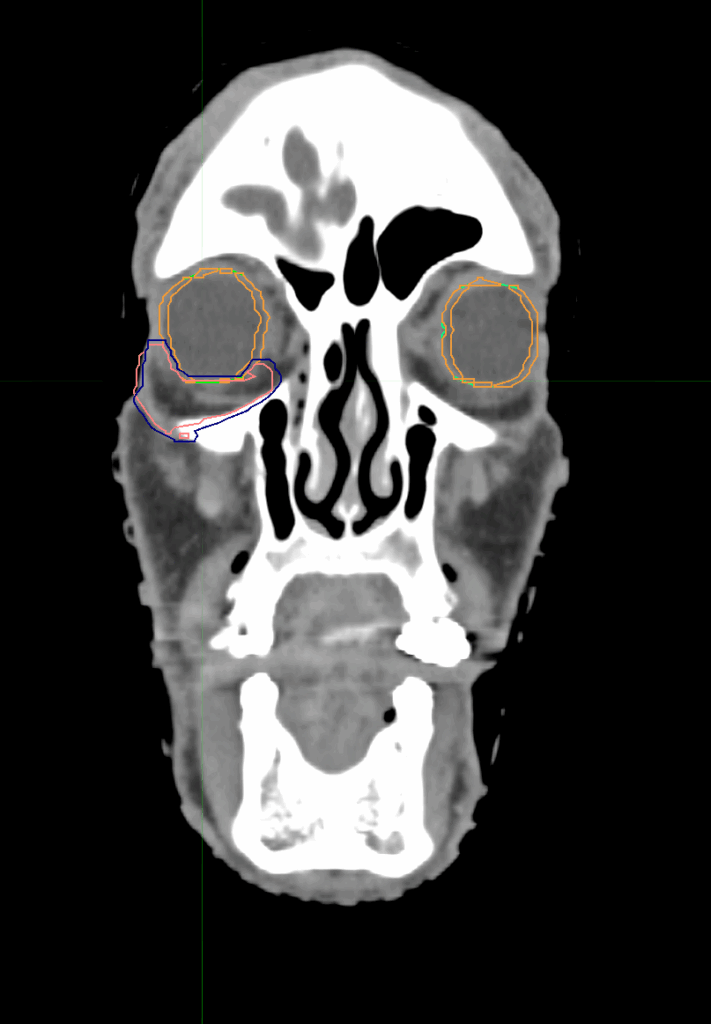

Planning CT Images

Treatment Planning Highlights

PTV(s) Volume

PTV, 7.4 cc

Dose Distributions

• Prescription to the 72% isodose line

• Max. dose 66 Gy